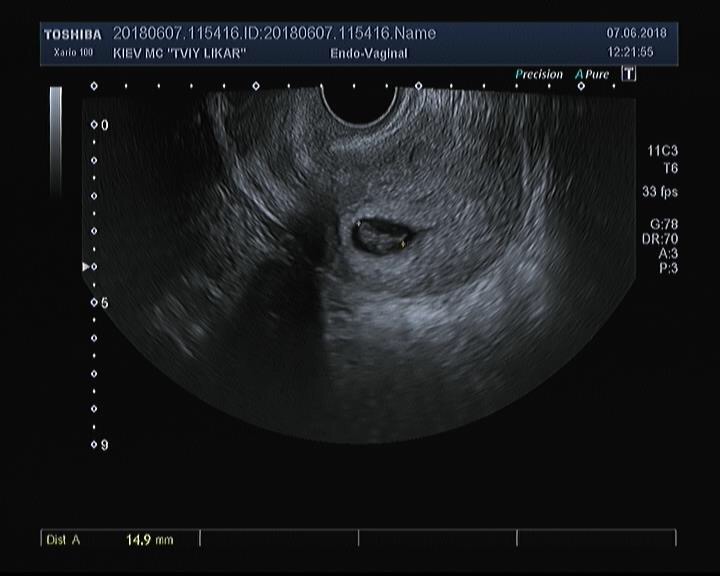

Была сегодня на узи. На данный момент все отлично. Если не считать круглосуточную тошноту и слабость.

ЧСС: 160 ударов

Эмбрион 14.9 мм. Гинеколог назвала его фасолью, но для меня он креветка.

Все развивается по сроку, но был небольшой тонус по задней стенке. Сказала, что не критично, так как я нервничаю и это вполне ожидаемо.

А вот и фото креветки))